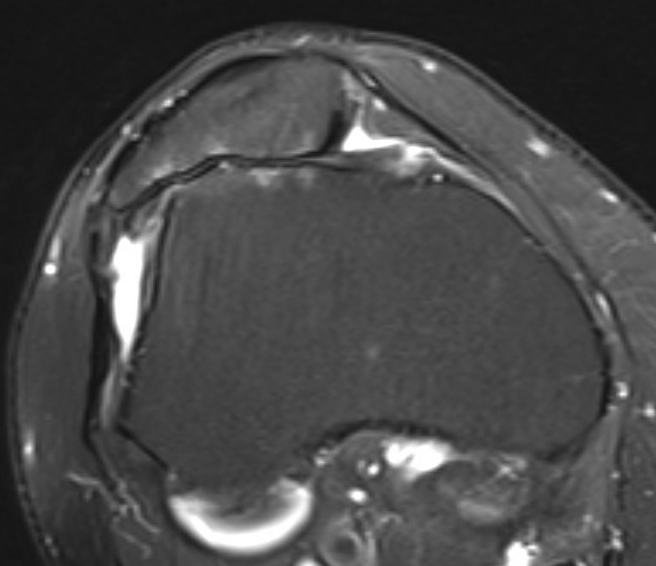

MRI

Severe lateral PFJ OA in the setting of maltracking / subluxation / tilt